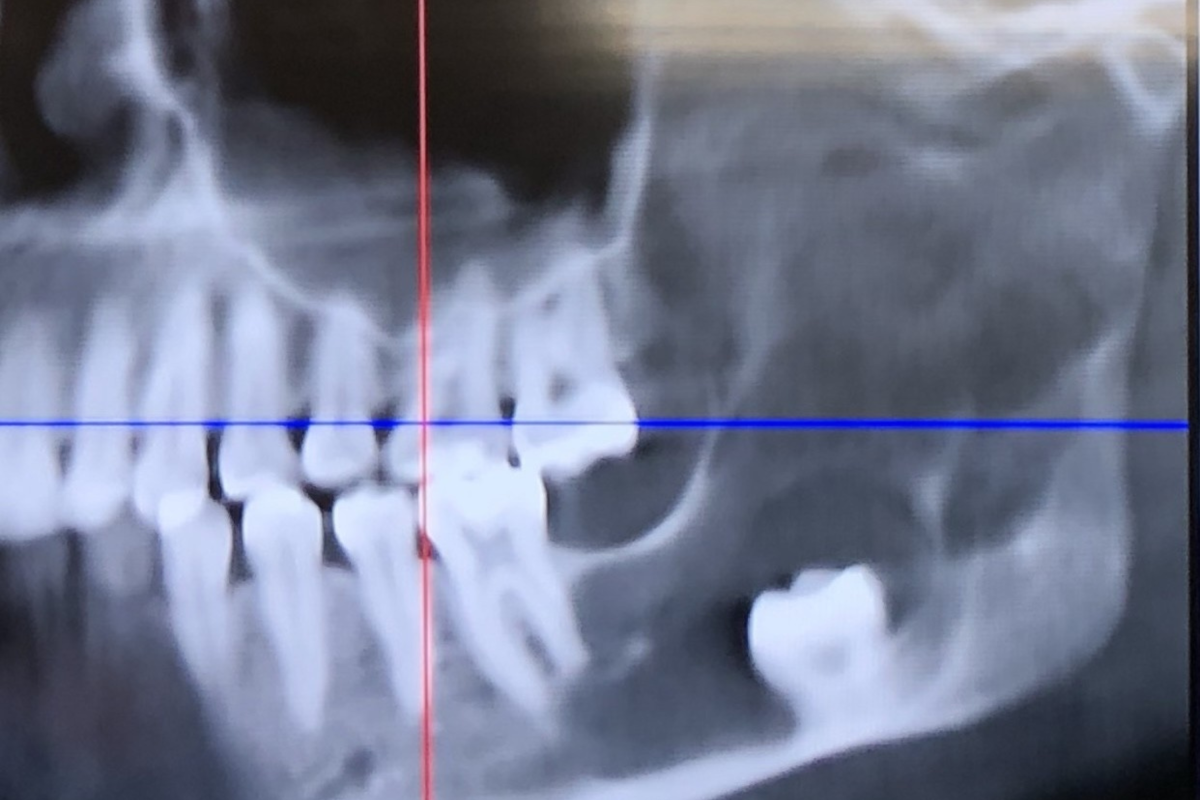

Andrea è stato indirizzato da un chirurgo orale per una TAC per capire meglio perché il dente si era spostato così lontano. I risultati hanno rivelato qualcosa di molto più grave di una semplice estrazione.

La scansione ha mostrato una ciste che cresceva all’interno del lato sinistro della mascella, probabilmente originata dalla sacca attorno al dente del giudizio incluso. La ciste è rimasta inosservata abbastanza a lungo da aver eroso gran parte della sua mascella, lasciandola pericolosamente fragile, fino alla cerniera.